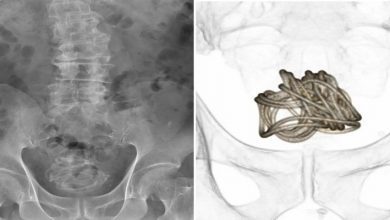

Une corde à sauter coincée dans la vessie d’un homme de 79 ans après l’avoir insérée par son p3nis

Un Japonais de 79 ans a eu une corde à sauter de 90 pouces coincée dans sa vessie après l’avoir…